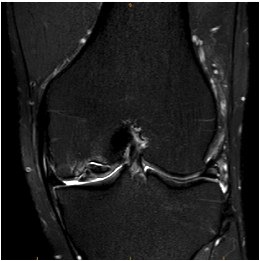

Location

Medial Femoral Condyle 85%

- lateral aspect of the MFC

- PCL origin

Lateral Femoral Condyle 10%

- most common in the central region of the LFC

Patellofemoral Joint 5%

- typically lateral trochlea